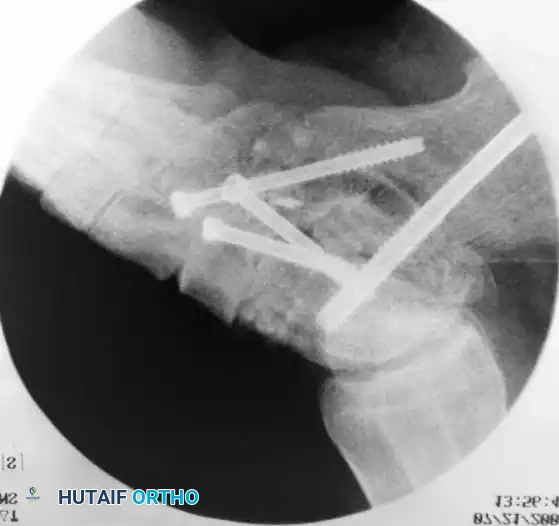

- Temporary Fixation: Use one or two 0.062-inch K-wires or a guidewire for temporary fixation.

- Definitive Fixation: In rheumatoid patients, osteopenic bone makes fixation challenging.

- Place a cannulated or noncannulated 6.5-mm or 7.0-mm partially threaded screw from the posterior aspect of the calcaneal tuberosity into the body of the talus.

- The entry point is ~1 cm lateral to the midline of the calcaneal tuberosity. The optimal trajectory exits the talus just distal to the body-neck junction, allowing the screw threads to grip the dense superior cortex of the talar neck.

- Use a washer to prevent the screw head from sinking into osteopenic calcaneal bone.

Intraoperative fluoroscopy confirming the trajectory and compression of the large-fragment cannulated screws across the subtalar arthrodesis site.